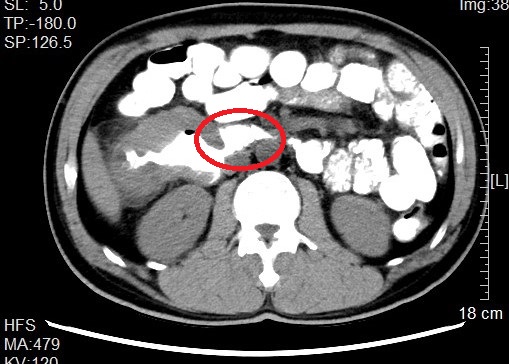

来自省内正值中年的邹先生和张先生都因“阵发性腹痛不适感”就医而发现结肠肿瘤,慕名转诊找到我院治疗。杨春康教授接诊,经过详细全面的检查后,发现二者的病情相似,都为升结肠近肝曲部的肿瘤且肿瘤已侵犯临近的重要脏器——十二指肠,全身其他部位没有发现肿瘤转移病灶,属于局部晚期病例。面对仍有治愈希望的病人以及家属的殷切希望,尽管病情高度复杂,手术风险和压力巨大,杨春康教授和他率领的医疗护理团队没有在困难面前退缩。在与病人及家属充分沟通后,决定为他们手术,并制定周密的手术方案。

杨春康主任介绍,患者的这种病情,按照目前国内多数医院的做法,大都就会直接放弃对病人的手术治疗,转而以全身化疗为主。但对于消化道的肿瘤,手术仍是目前唯一可能彻底治愈疾病的手段;此类患者要达到手术根治目的,必须做联合胰十二指肠切除的扩大右半结肠癌根治手术。一个右半结肠癌根治就已经是一个大型手术了,而胰十二指肠切除则更是一个腹部外科领域极限的特大型手术。这样的两个大型手术一起做,光光其手术的复杂性、难度系数、风险系数均是巨大的,而且术后发生包括吻合口漏在内的各种严重并发症风险极高。这既是对病人自身身体耐受能力的极限挑战,也是对主刀医生及其团队的技术、能力和医院多学科综合实力的极大挑战。如果放弃手术,病人基本难以获得较长的生存期。